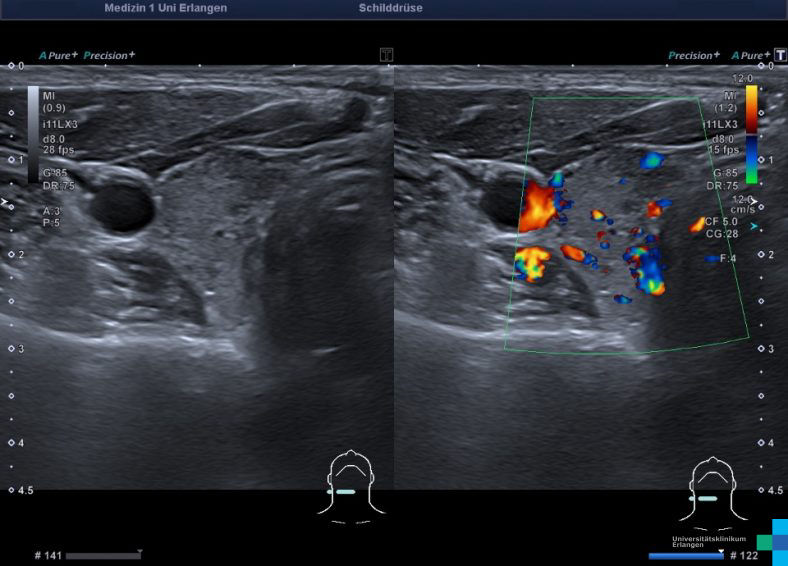

SDD_AIT_XXX_1201.jpg